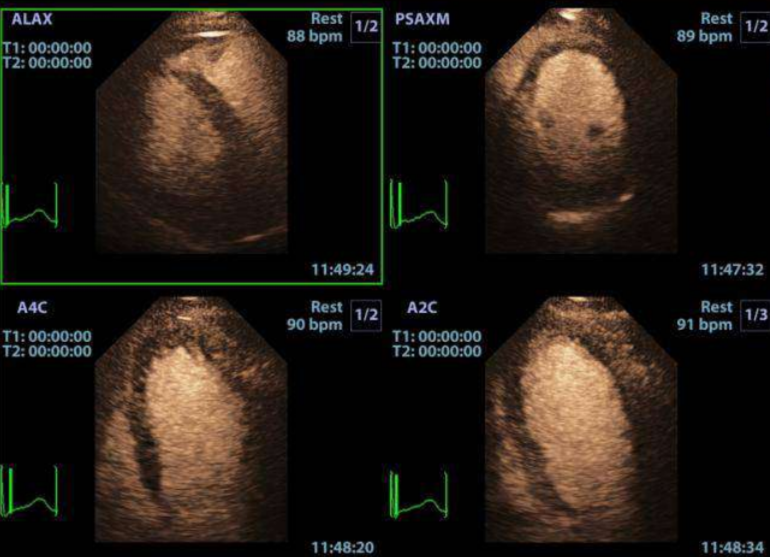

Ecógrafo Mindray M9

Detalles del producto

Características